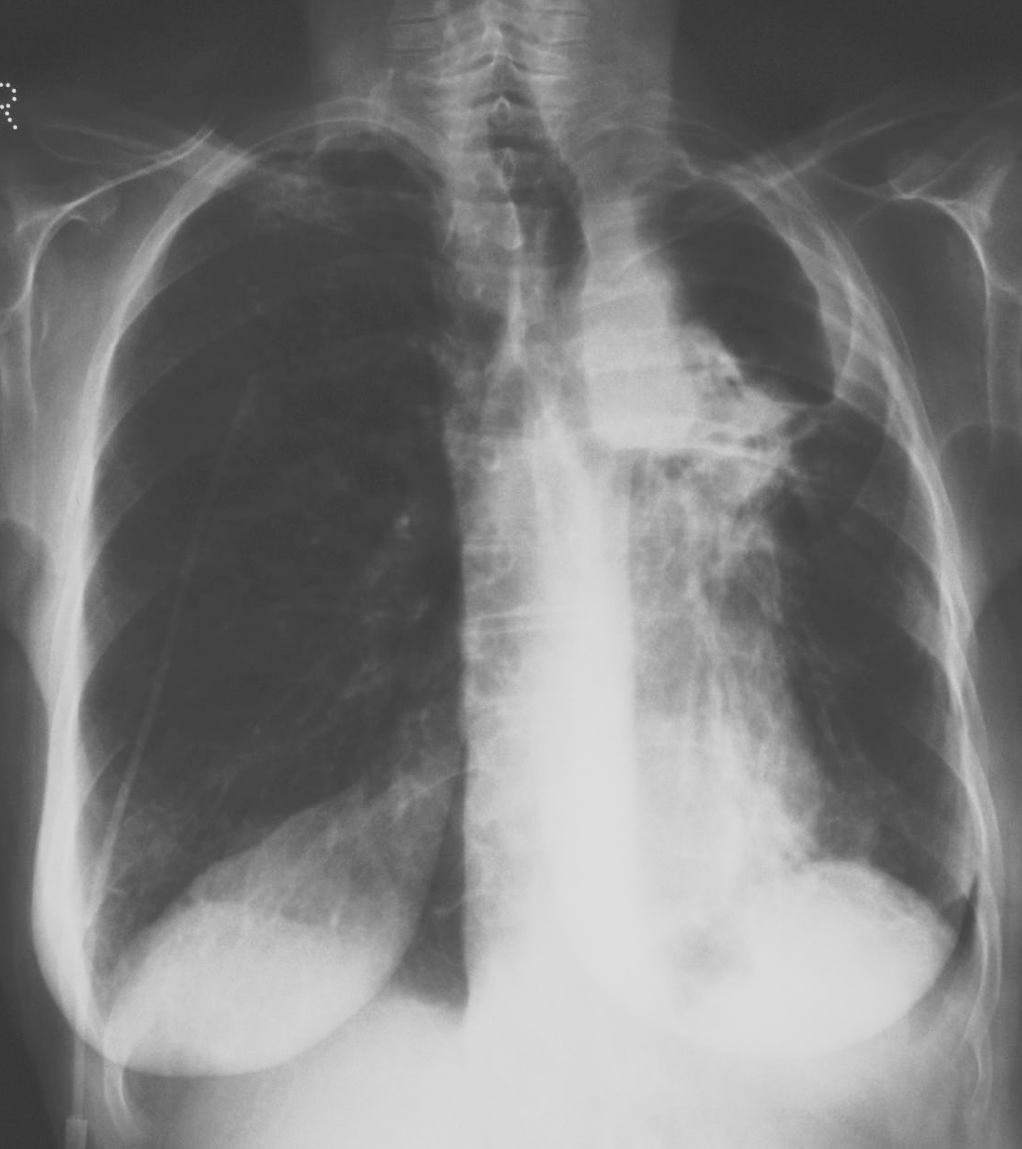

What is this ?

Chronic cavitary pulmonary aspergillosis

-left apical cavity due to CCA

-In CCA, the cavity exists first, aspergiloma grows, cavity expands through damage n inflammation n stuff

-roling fungal balls cann cause problems

-other lung evebtually fibroses